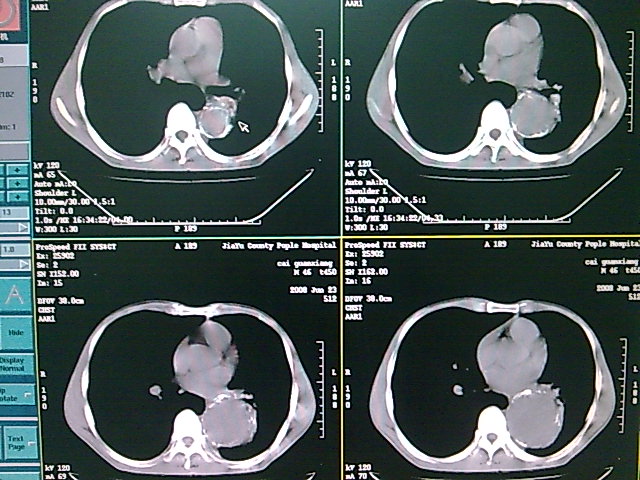

以下是引用dyqct在2008-6-27 14:37:00的发言:[br]支持胸主动脉瘤,建议增强进一步检查。

以下是引用zsl6918在2008-6-27 14:24:00的发言:[br]动脉瘤